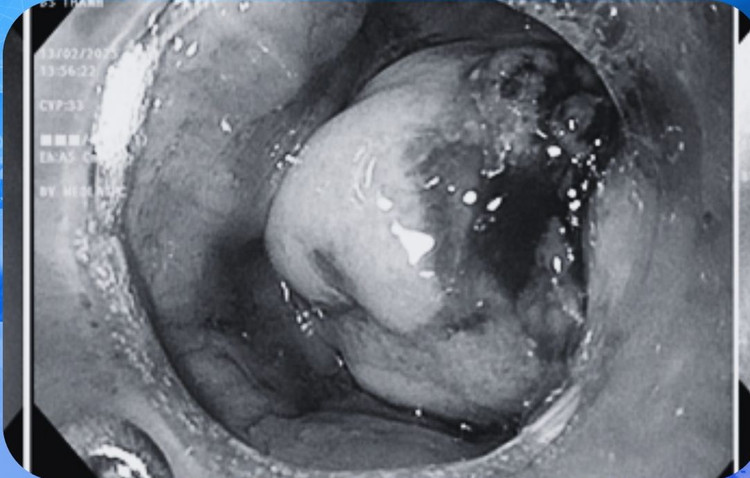

Qua thăm khám, trên siêu âm tuyến giáp, bác sĩ tình cờ phát hiện u thực quản phía sau tuyến giáp. Khi khai thác thêm triệu chứng, phát hiện bệnh nhân trước đây đã có cảm giác nuốt vướng nhưng không thường xuyên và mơ hồ nên đã bỏ qua, cân nặng đến nay đã giảm 3kg. Sau đó, khi nội soi thực quản phát hiện một khối lớn vùng thực quản bên trên có vùng loét, nghi ngờ ung thư.

Hình ảnh chụp CT-Scanner bổ sung sau đó nghĩ tới ung thư thực quản đoạn cổ và có một số hạch bất thường vùng cổ.

| Hình ảnh chụp phát hiện khối ung thư tế bào vảy sừng. Ảnh BVCC |

Kết quả giải phẫu bệnh khối u sau đó cho thấy hình ảnh ung thư tế bào vảy sừng hoá xâm nhập.

Dựa vào kết quả lâm sàng và cận lâm sàng đã thực hiện, bệnh nhân Q. được chẩn đoán xác định mắc ung thư thực quản giai đoạn T3N1M0.